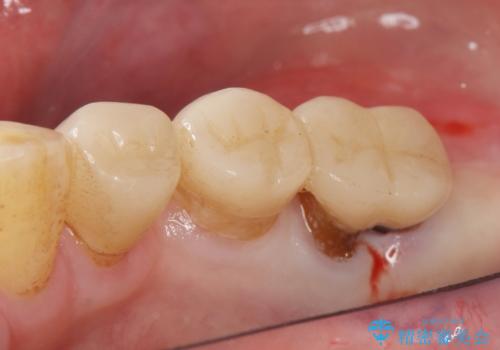

- 奥歯の違和感を主訴に来院された患者様です。

精査したところ、右下の奥歯は大きなう蝕により保存不可能な状態でした。

患者様のご希望により、抜歯後インプラント治療を行いました。